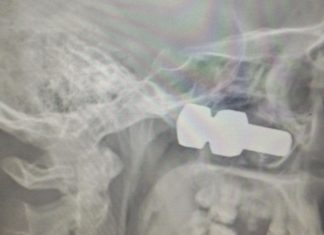

З-під колеса вантажівки вилетів болт, який потрапив в голову

Якщо ви дивилися фільм «Пункт призначення», то після прочитання цього поста вам стане ще страшніше виходити на вулицю. Житель Лесосибирска чекав на трасі свого...